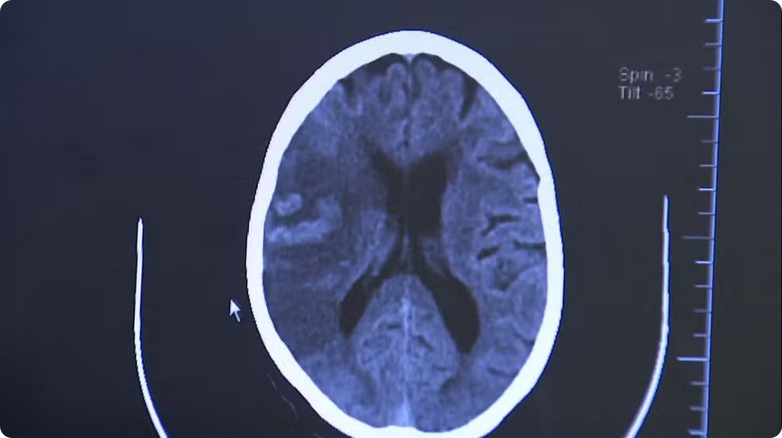

A droga K9 é uma das mais mortais da atualidade, e pode causar danos irreversíveis ao cérebro e ao coração. É uma mistura de cocaína, heroína e fentanil, um opióide sintético que é 50 vezes mais potente que a morfina.